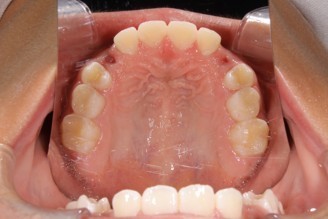

1期矯正治療の症例写真

1期矯正治療終了後の症例写真

第2大臼歯萌出完了

• 主訴:歯がガタガタで気になる

• 診断あるいは主な症状:叢生

• 年齢:12歳(治療開始年齢)

• 治療に用いた主な装置:マルチブラケットによる歯列矯正(小児矯正)

• 抜歯部位:なし

• 治療期間:2年8ヶ月

• 治療回数:35回(矯正治療を目的とした来院)

• 治療費概算:932,000円(税込)